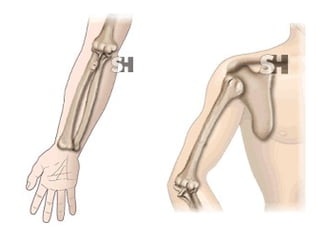

• #11 Fx desplazada 1/3 distal del peroné. Fractura trocánter mayor del fémur.